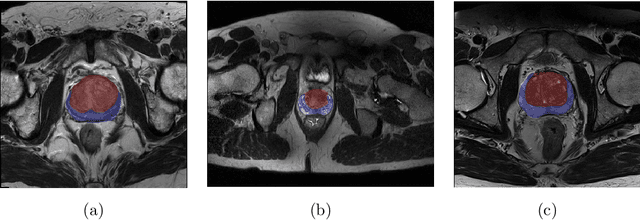

Abstract:Prostate cancer is the most common malignant tumors in men but prostate Magnetic Resonance Imaging (MRI) analysis remains challenging. Besides whole prostate gland segmentation, the capability to differentiate between the blurry boundary of the Central Gland (CG) and Peripheral Zone (PZ) can lead to differential diagnosis, since tumor's frequency and severity differ in these regions. To tackle the prostate zonal segmentation task, we propose a novel Convolutional Neural Network (CNN), called USE-Net, which incorporates Squeeze-and-Excitation (SE) blocks into U-Net. Especially, the SE blocks are added after every Encoder (Enc USE-Net) or Encoder-Decoder block (Enc-Dec USE-Net). This study evaluates the generalization ability of CNN-based architectures on three T2-weighted MRI datasets, each one consisting of a different number of patients and heterogeneous image characteristics, collected by different institutions. The following mixed scheme is used for training/testing: (i) training on either each individual dataset or multiple prostate MRI datasets and (ii) testing on all three datasets with all possible training/testing combinations. USE-Net is compared against three state-of-the-art CNN-based architectures (i.e., U-Net, pix2pix, and Mixed-Scale Dense Network), along with a semi-automatic continuous max-flow model. The results show that training on the union of the datasets generally outperforms training on each dataset separately, allowing for both intra-/cross-dataset generalization. Enc USE-Net shows good overall generalization under any training condition, while Enc-Dec USE-Net remarkably outperforms the other methods when trained on all datasets. These findings reveal that the SE blocks' adaptive feature recalibration provides excellent cross-dataset generalization when testing is performed on samples of the datasets used during training.

Abstract:Prostate cancer is the most common cancer among US men. However, prostate imaging is still challenging despite the advances in multi-parametric Magnetic Resonance Imaging (MRI), which provides both morphologic and functional information pertaining to the pathological regions. Along with whole prostate gland segmentation, distinguishing between the Central Gland (CG) and Peripheral Zone (PZ) can guide towards differential diagnosis, since the frequency and severity of tumors differ in these regions; however, their boundary is often weak and fuzzy. This work presents a preliminary study on Deep Learning to automatically delineate the CG and PZ, aiming at evaluating the generalization ability of Convolutional Neural Networks (CNNs) on two multi-centric MRI prostate datasets. Especially, we compared three CNN-based architectures: SegNet, U-Net, and pix2pix. In such a context, the segmentation performances achieved with/without pre-training were compared in 4-fold cross-validation. In general, U-Net outperforms the other methods, especially when training and testing are performed on multiple datasets.